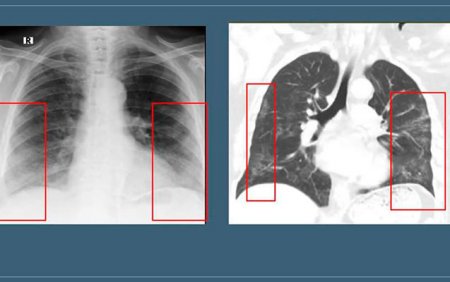

Hər kəsi qorxuya salan “buzlu şüşə” diaqnozu nə deməkdir? - FOTO